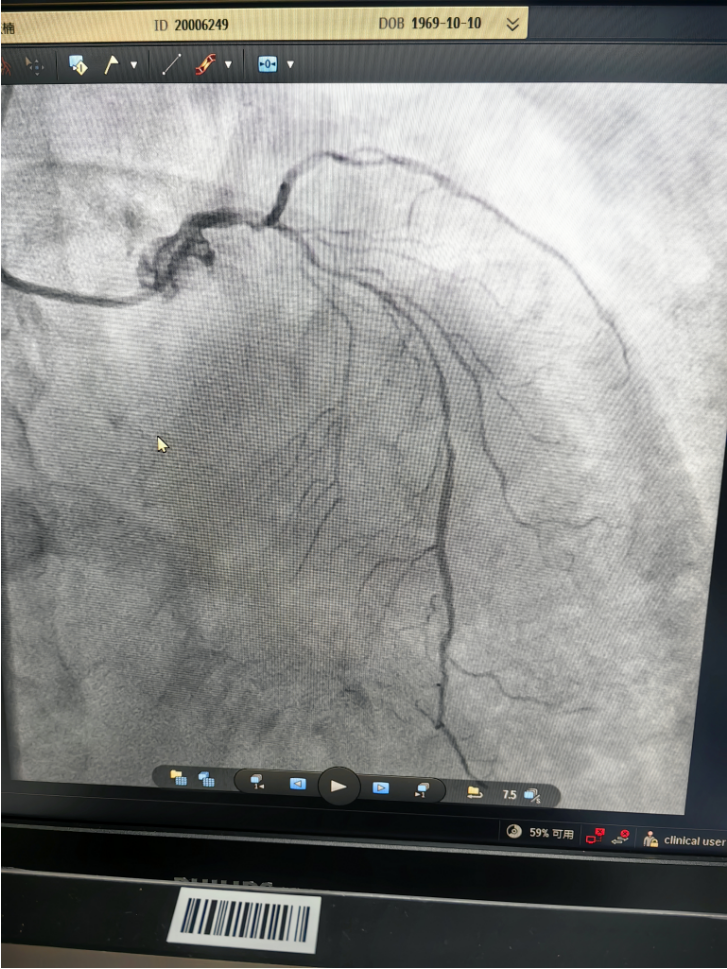

4月21日,在心血管内科主任王景峰教授的指导下,在花都院区DSA(数字减影血管造影)介入平台的配合以及IABP(主动脉内球囊反搏)的辅助下,林茂欢副主任医师带领曹正宇助理研究员和王春红主管护师成功抢救一例急性心梗合并急性左心衰的重症患者,顺利完成急诊介入手术。

据悉,患者为55岁女性,因血糖控制不佳就诊。住院期间,她突发胸痛,诊断为急性非ST段抬高型心肌梗死,其冠脉三支血管严重病变,其中一支血管完全闭塞,术中出现急性左心衰发作,病情危急。团队迅速启动抢救预案,在药物抢救的基础上及时置入IABP辅助循环治疗,经过半个小时的积极抢救,患者转危为安,生命体征稳定。

术前(左一、左二)、术后(右一)